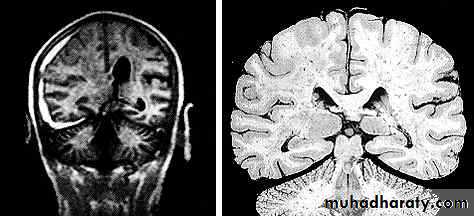

1. Diffuse Axonal Injury

Prolonged post-traumatic state in which there is loss of consciousness from the time of injury that continues beyond 6 hours.

Occurs as a result of mechanical shearing at the grey-white matter interface.

This causes disruption and tearing of axons, myelin sheaths and blood capillaries.

Severity can range from mild damage with confusion to coma and even death.